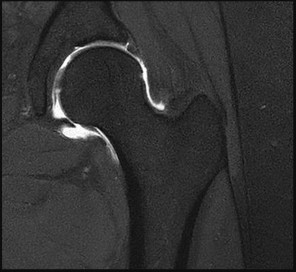

A 45-year-old female sustains a knee injury following a motor vehicle collision. Assuming the representative image demonstrates a medial tibial plateau fracture with articular depression (Schatzker IV), what is the most likely mechanism of injury?

A Schatzker IV fracture involves the medial tibial plateau. The medial plateau is structurally denser and stronger than the lateral plateau, meaning fractures here typically require higher energy. The classic mechanism is a varus force combined with an axial load. In contrast, lateral plateau fractures (Schatzker I-III) are typically caused by a valgus force with an axial load. High-energy trauma to the medial plateau is also highly associated with injury to the peroneal nerve, popliteal artery, and ligamentous structures (like the ACL or LCL).